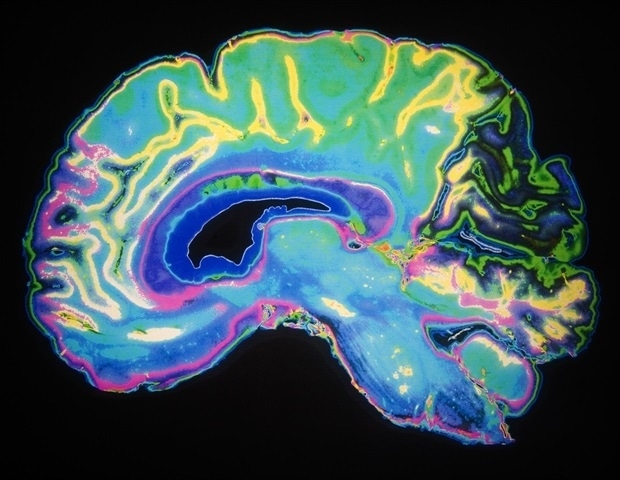

Many research groups have made progress in recent years by tracing amyloid's path in the brain using technologies such as positron emission tomography and by looking at brains post-mortem, but the new study adds substantial new evidence from the 5XFAD mouse model because it presents an unbiased look at the entire brain as early as one month of age.The study reveals that amyloid begins its terrible march in deep brain regions such as the mammillary body, the lateral septum and the subiculum before making its way along specific brain circuits that ultimately lead it to the hippocampus, a key region for memory, and the cortex, a key region for cognition.

The team used SWITCH, a technology developed by Chung, to label amyloid plaques and to clarify the whole brains of 5XFAD mice so that they could be imaged in fine detail at different ages. The team was consistently able to see that plaques first emerged in the deep brain structures and then tracked along circuits such as the Papez memory circuit to spread throughout the brain by 6-12 months (a mouse's lifespan is up to three years).

Importantly, the team directly validated a key prediction of their mouse findings in human tissue: If the mammillary body is indeed a very early place that amyloid plaques emerge, then the density of those plaques should increase in proportion with how far advanced the disease is. Sure enough, when the team used SWITCH to examine the mammillary bodies of post-mortem human brains at different stages of the disease, they saw exactly that relationship: The later the stage, the more densely plaque-packed the mammillary body was."This suggests that human brain alterations in Alzheimer's disease look similar to what we observe in mouse," the authors wrote. "Thus we propose that amyloid-beta deposits start in susceptible subcortical structures and spread to increasingly complex memory and cognitive networks with age."